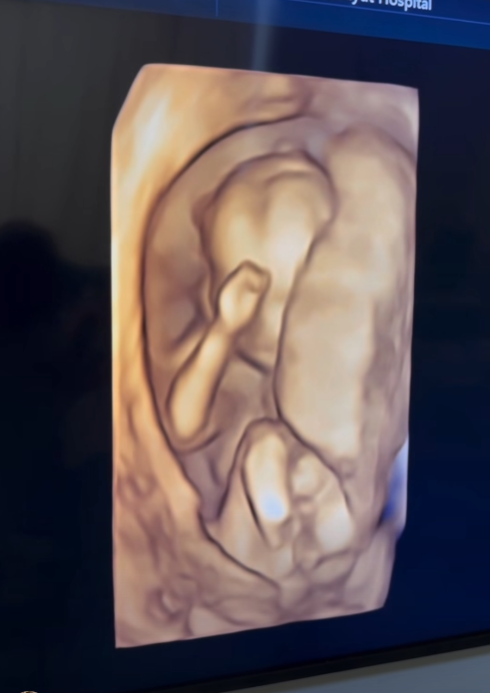

เรียกได้ว่าเป็นช่วงเวลาแห่งความสุขแบบคูณสองของครอบครัว ลอยชูศักดิ์ เลยทีเดียว เมื่อคุณแม่คนสวยอย่าง ครูก้อย นัชชา ลอยชูศักดิ์ ภรรยาสุดที่รักของ เจมส์ เรืองศักดิ์ ลอยชูศักดิ์ ออกมาอัปเดตการตั้งครรภ์โชว์ท้องที่เริ่มป่องอย่างเห็นได้ชัด หลังตั้งครรภ์ลูกสาวคนที่สองได้ 17 สัปดาห์ พร้อมโชว์ภาพอัลตราซาวด์ที่เผยให้เห็นว่าเบบี๋ตัวยาวสมบูรณ์สุดๆ แถมมีแววจะตัวสูงตามรอยพี่สาวอย่าง น้องเมดา มาติดๆ